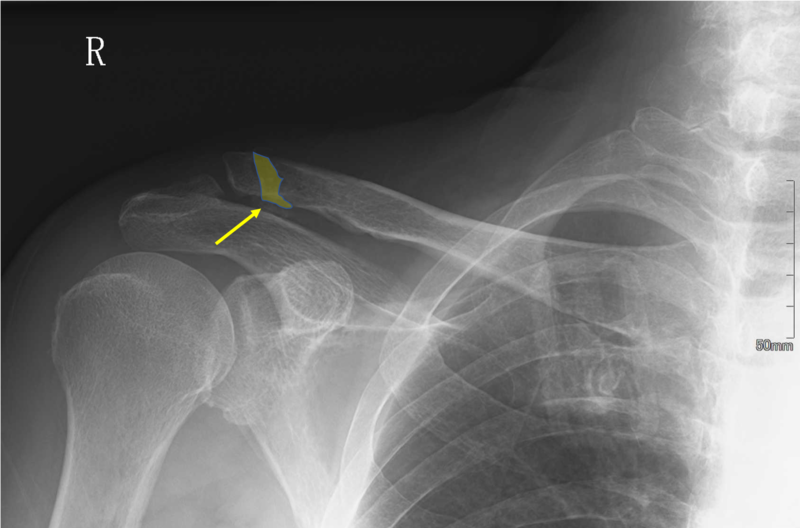

例)鎖骨遠位端骨折の偽関節

黄矢印:鎖骨遠位端骨折後の偽関節部